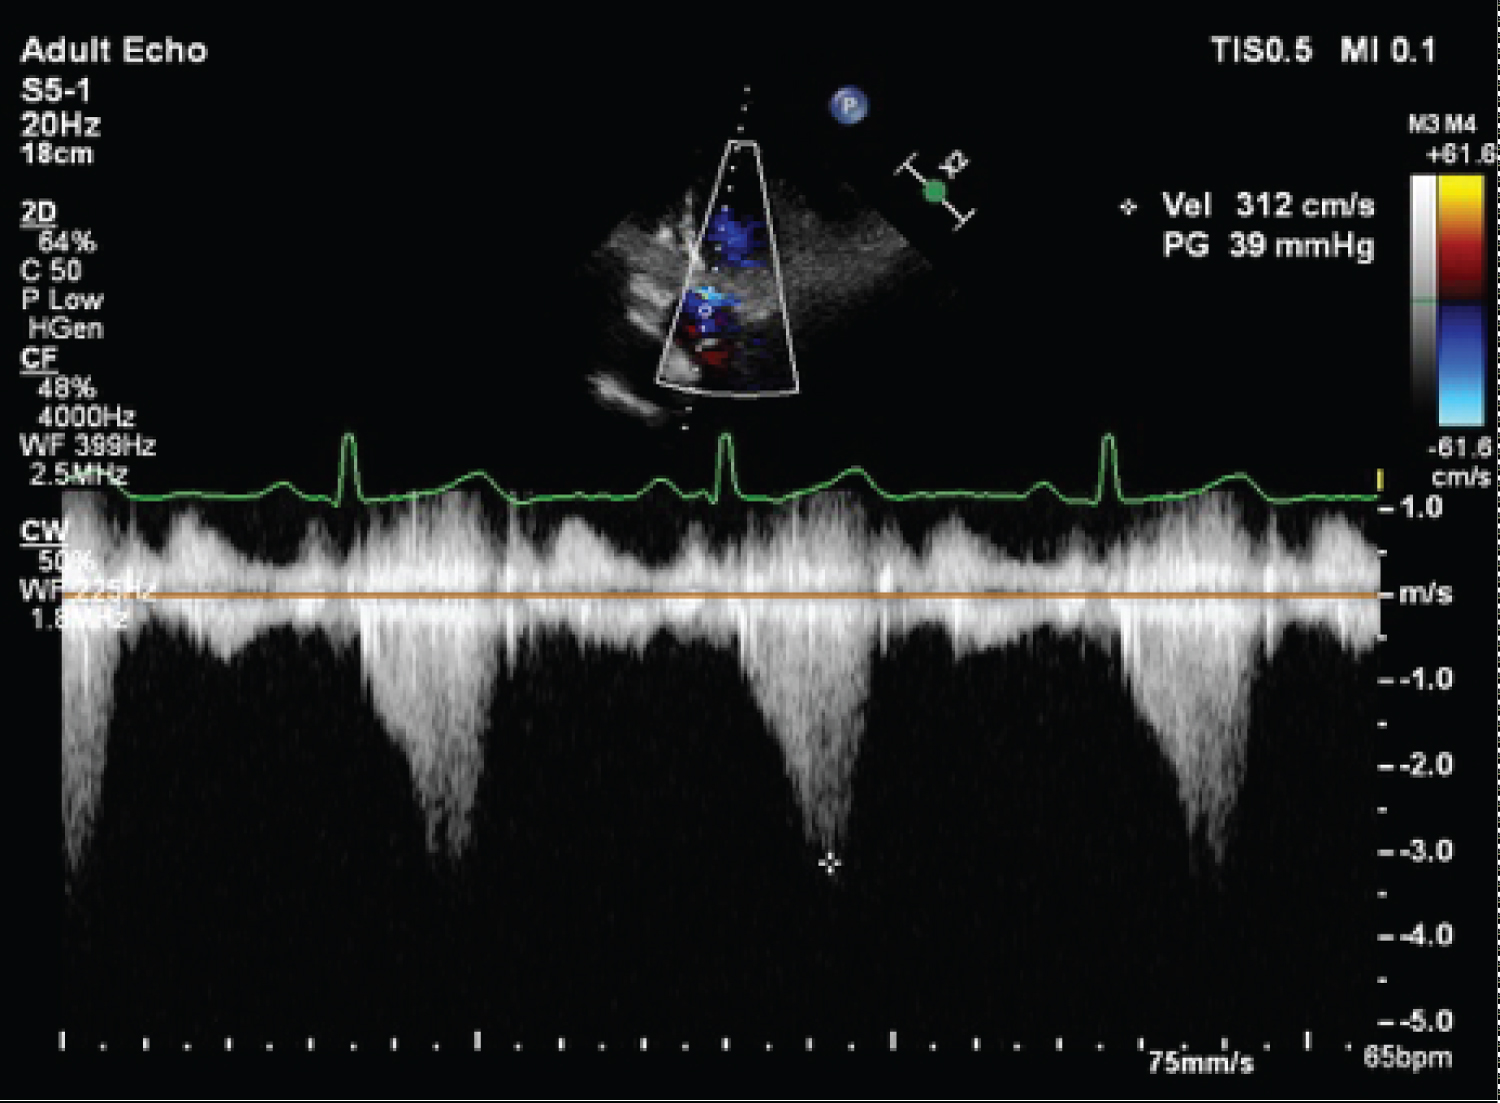

A 70-year-old Chinese female with underlying hypertension, hyperlipidemia and diabetes mellitus presented to the outpatient clinic with exertional dyspnoea. There was no family history of hypertrophic cardiomyopathy or sudden cardiac death. Physical examination revealed normal sinus rhythm with a systolic murmur. Transthoracic echocardiography showed a non-dilated left ventricle with a sigmoid septum (maximal thickness of 15 mm) (Figure 1). The left ventricular ejection fraction was 60%. There was SAM of the mitral valve resulting in significant LVOTO (Figure 2 and Figure 3), with peak pressure gradient of 39 mmHg at rest, which rose to 78 mmHg with bicycle exercise (Figure 4 and Figure 5). There was also moderate to severe mitral regurgitation. The length of the anterior mitral leaflet was 2.2 centimetres, and the aorto-LV angle was measured at 121 degrees. An incidental inter-atrial septum mass on the left atrium was also noted, suggestive of an atrial myxoma. She was started on beta-blockade for symptom relief, but despite that remained very symptomatic.

Figure 4: Peak LVOT gradient (39 mmHg) at rest. View Figure 4